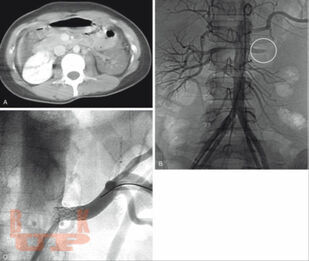

В монографии изложены современные рекомендации по диагностике и лечению сочетанной закрытой травмы живота, основанные на отечественных и зарубежных публикациях из электронных баз медицинской литературы PubMed, Cochrane Library, Scopus, Embase, ScienceDirect, Google Scholar Search, eLibrary, анализе многоцентровых исследований, систематических обзоров, метаанализов, больших серий случаев, оригинальных статей и рандомизированных контролируемых исследований с указанием уровней доказательств и силы рекомендаций.

Предложен оригинальный алгоритм диагностики и лечебной тактики при сочетанной закрытой травме живота, позволяющий стандартизировать ведение данных пациентов, дана детализация данного алгоритма при повреждении конкретных органов и систем, описана концепция damage control, уточнены показания к методам диагностики, консервативному лечению, видам оперативных, эндоваскулярных и малоинвазивных вмешательств в зависимости от степени тяжести травмы органов.